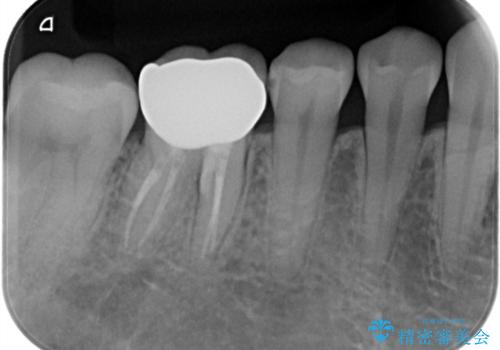

【精密根管治療】間違った根管形成→パフォレーションリペアによる修復

根管内を見てみると、近心根は本来の根管とは違うところを削られて髄床底でパーフォレーションを起こしていました。

また、遠心根でも本来の根管とは逸脱した方向に根管形成されていましたが、修正し充填を行っています。

パーフォレーション部位に関しては、口腔内との交通がなければMTAセメントを用いて修復することで、高い予知性を期待できます。